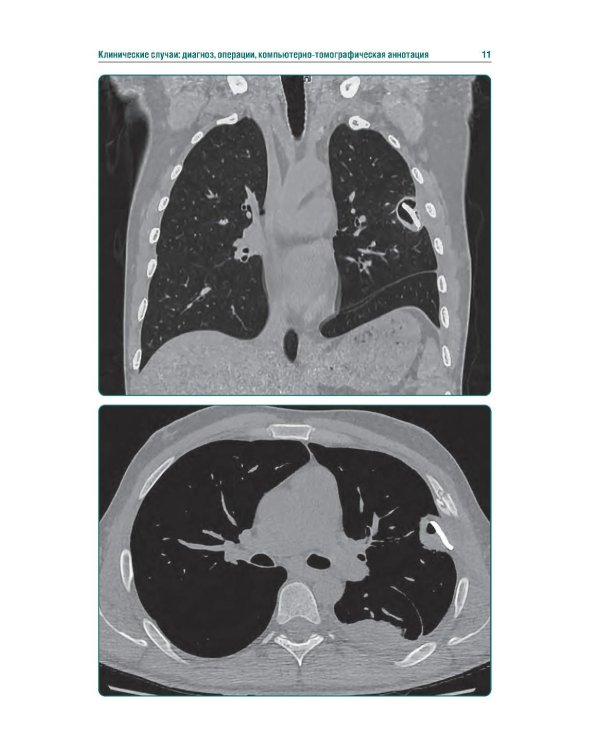

Издание представляет собой первый в Российской Федерации атлас, иллюстрирующий различные виды поражения легких, плевры и других структур грудной клетки у пациентов с боевыми ранениями. В современных условиях количество таких пациентов увеличивается, поэтому существенно возрастает значимость различных видов боевых травм, в том числе повреждений грудной клетки. В атласе представлены уникальные КТ-изображения различных видов боевой травмы грудной клетки, полученных в условиях современных вооруженных конфликтов. Помимо описания характера, условий получения травмы и выявленных повреждений, есть возможность просмотра изображений в формате DICOM. Атлас предназначен для врачей-рентгенологов, торакальных хирургов, пульмонологов, а также врачей других специальностей, занимающихся диагностикой и лечением пациентов с боевыми травмами.| Издательство | ГЭОТАР-Медиа |